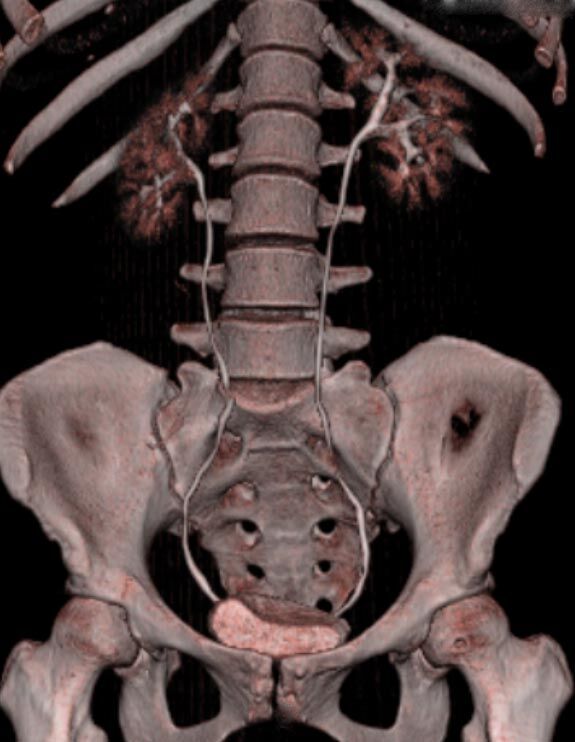

Abdomen (Bauch und Becken)

• Diagnostik von entzündlichen und tumorösen Erkrankungen der Bauchorgane

• Diagnostik von akuten Notfällen wie Darmverschluss, Hohlorganperforation oder Traumafolgen

• Darstellung der großen Gefäße zur Erkennung von Gefäßverschlüssen (z. B. Mesenterial - Arterienembolie oder Einengungen von Gefäßen (z. B. Nierenarterien)

• Darstellung und Therapieplanung von Aneurysmen (CT- Angiographie)

• Virtuelle Kolonographie zur Darstellung des Dickdarmes z. B. bei Kontraindikation zur Darm-Spiegelung oder nur unvollständig durchführbarer Koloskopie.

• mehrdimensionale Darstellung vasculärer Strukturen mit zahlreichen Auswertungstools